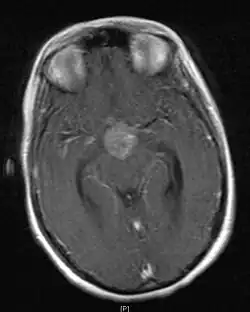

• Mainly located in midline structures, suprasellar region or pineal gland, also basal ganglia and hypothalamus

• Natural spread believed to be along subependymal lining of 3rd and 4th ventricles, leading to intraventricular relapse before spinal dissemination

Location

• Whole ventricular volume: 3rd, 4th, lateral, prepontine cistern